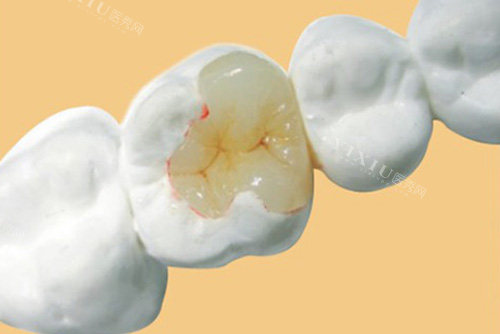

嵌体是一种嵌入牙体内部,用以修养牙体缺损的形态和功能的修复体。它与传统补牙相比,有很多优势。首先,嵌体是在模型上制作完成的,能够更正确地贴合牙齿的缺损部位,边缘密合度高,这大大降低了继发龋的发生几率。

而且,嵌体的材料通常具有更好的耐磨性和强度,能够承受更大的咀嚼压力,不易折断或磨损。从美观角度来看,嵌体可以根据患者牙齿的颜色进行选择,达到与天然牙齿相近的色泽,几乎可以做到以假乱真。